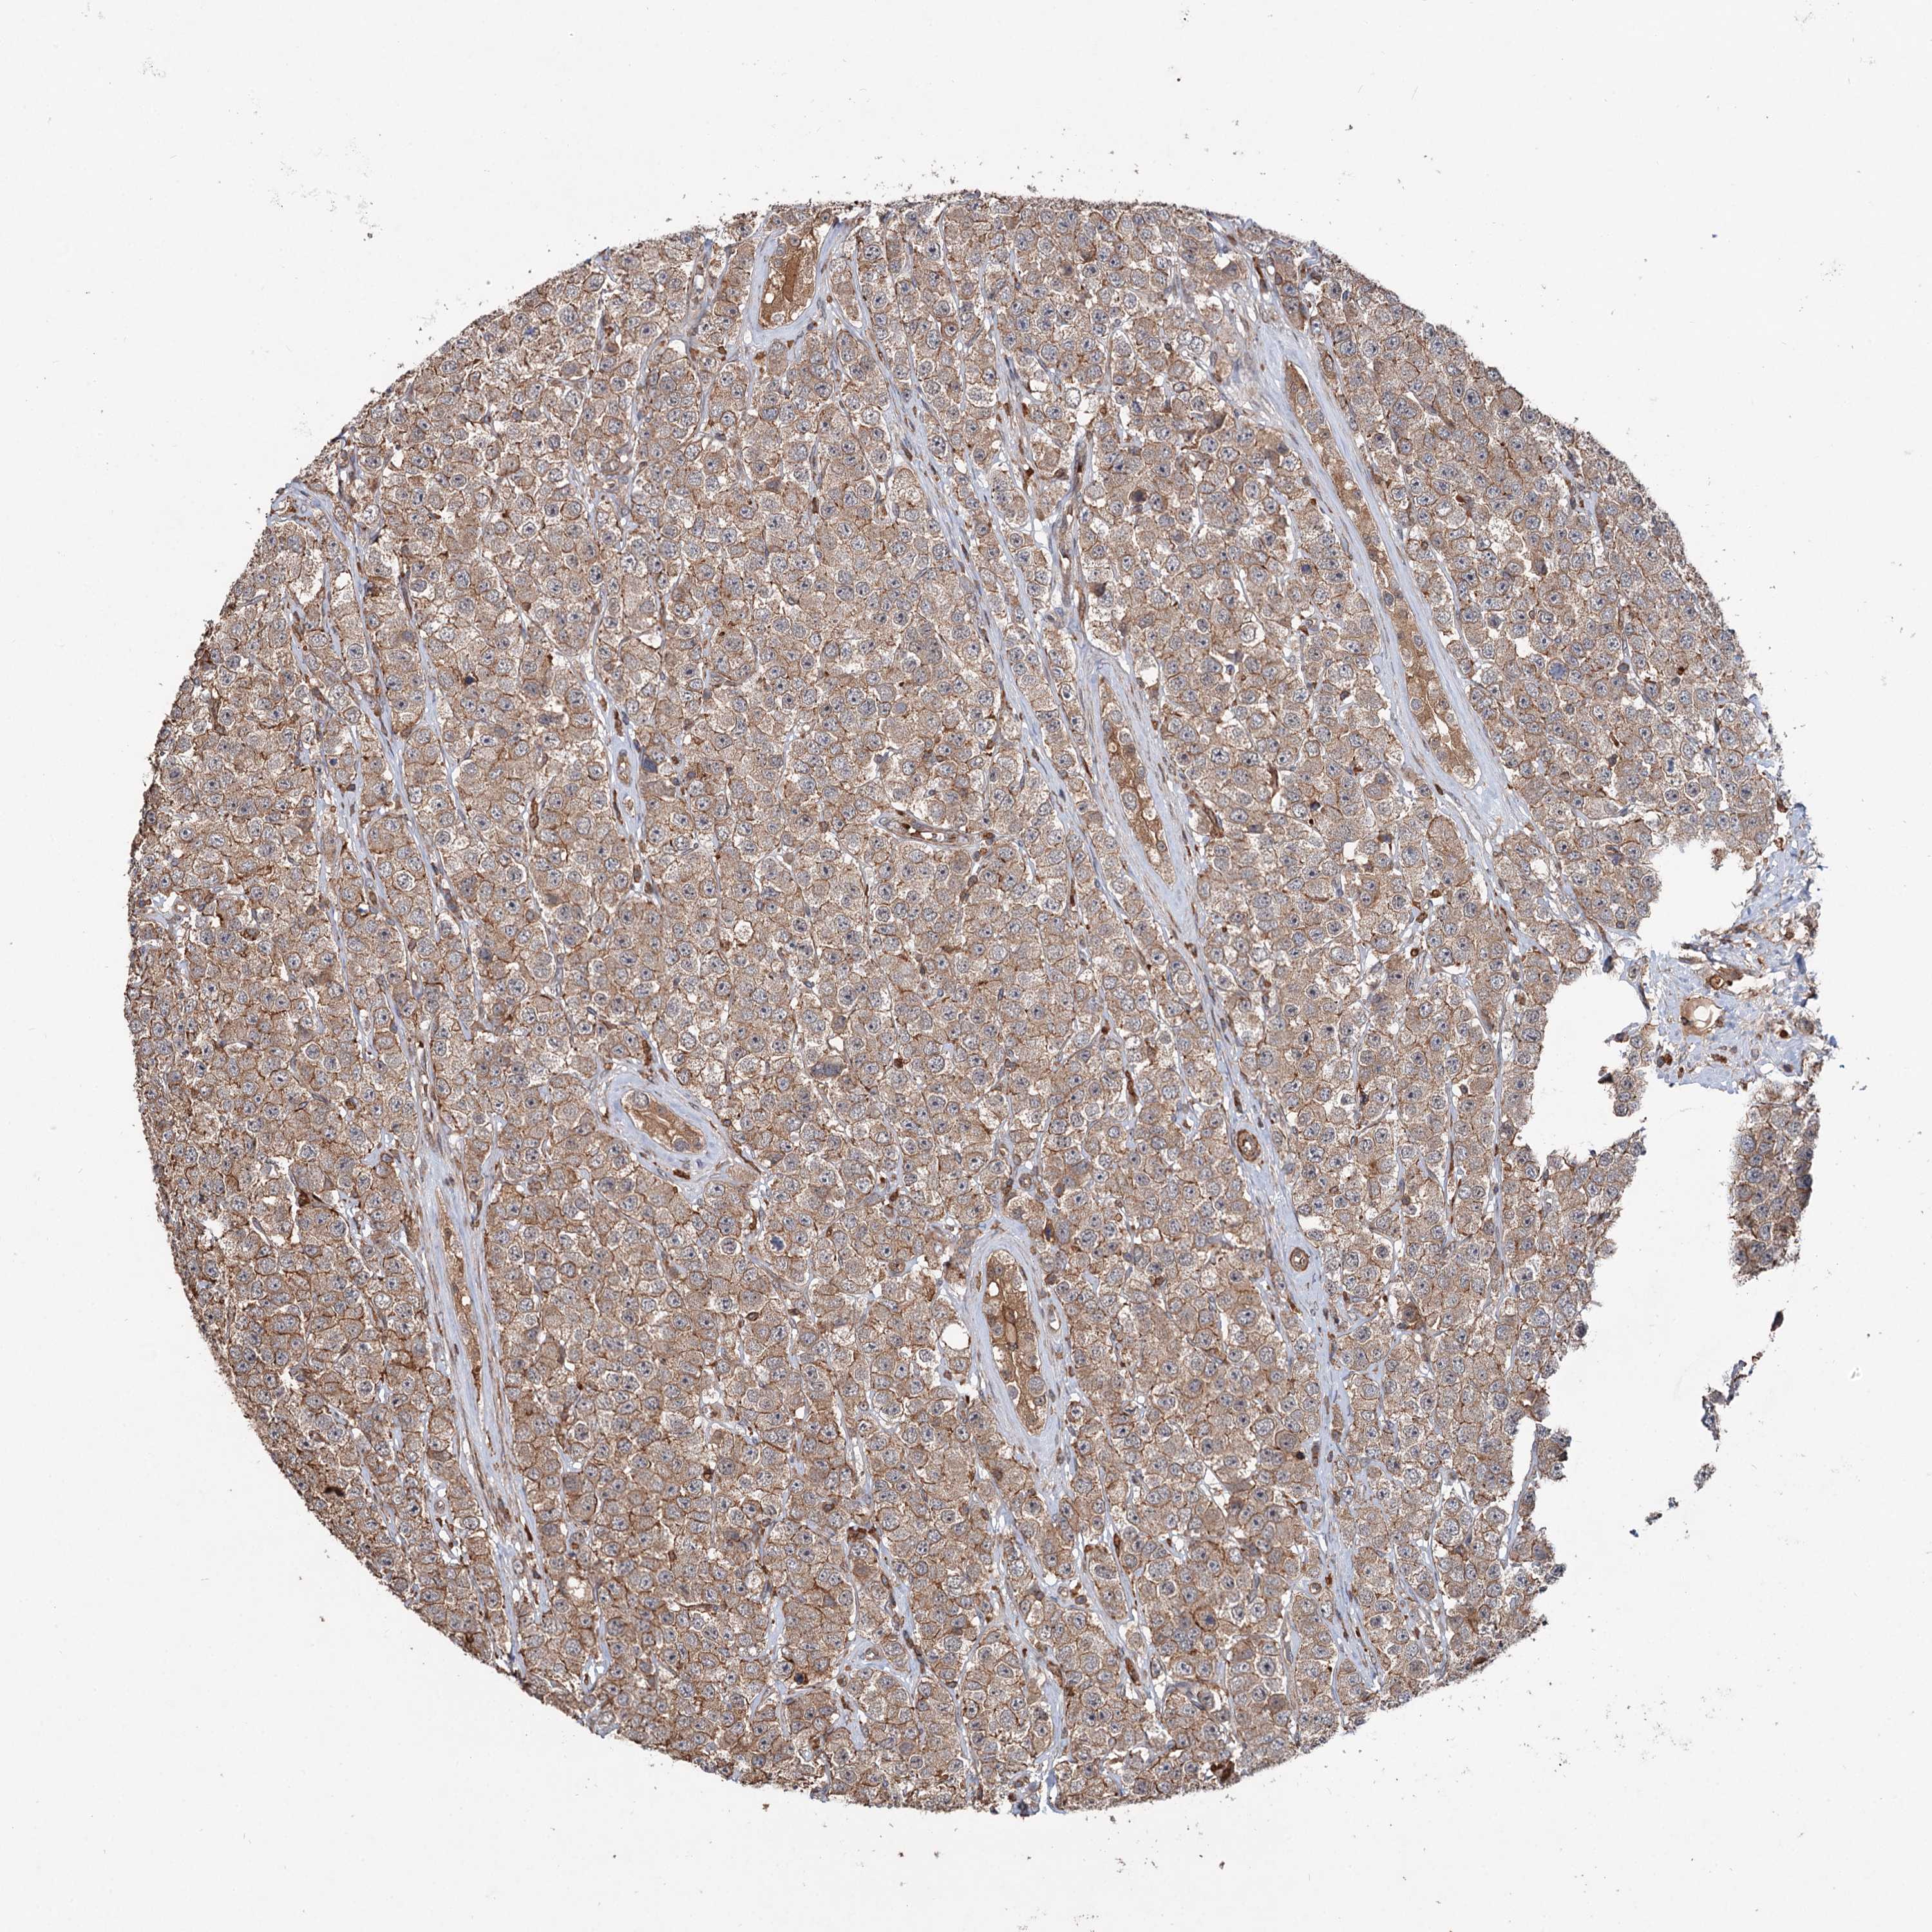

TESTIS CANCER - Protein expressioni

A mouse-over function shows sample information and annotation data. Click on an image to view it in a full screen mode. Samples can be filtered based on level of antibody staining by selecting one or several of the following categories: high, medium, low and not detected. The assay and annotation is described here.

Note that samples used for immunohistochemistry by the Human Protein Atlas do not correspond to samples in the TCGA dataset.

Antibody stainingi

Antibody staining in the annotated cell types in the current human tissue is reported as not detected, low, medium, or high, based on conventional immunohistochemistry profiling in selected tissues. This score is based on the combination of the staining intensity and fraction of stained cells.

Each image is clickable and will lead to virtual microscopy that enables deeper exploration of all samples and also displays staining intensity scores, fraction scores and subcellular localization as well as patient and tissue information for each sample.

Antibody HPA038856

Staining

High

Medium

Low

Not detected

Intensity

Strong

Moderate

Weak

Negative

Quantity

>75%

75%-25%

<25%

None

Location

Nuclear

Cytoplasmic/membranous

Cytoplasmic/membranous,nuclear

Carcinoma, Embryonal, NOS

Seminoma, NOS

Urothelial carcinoma, High grade